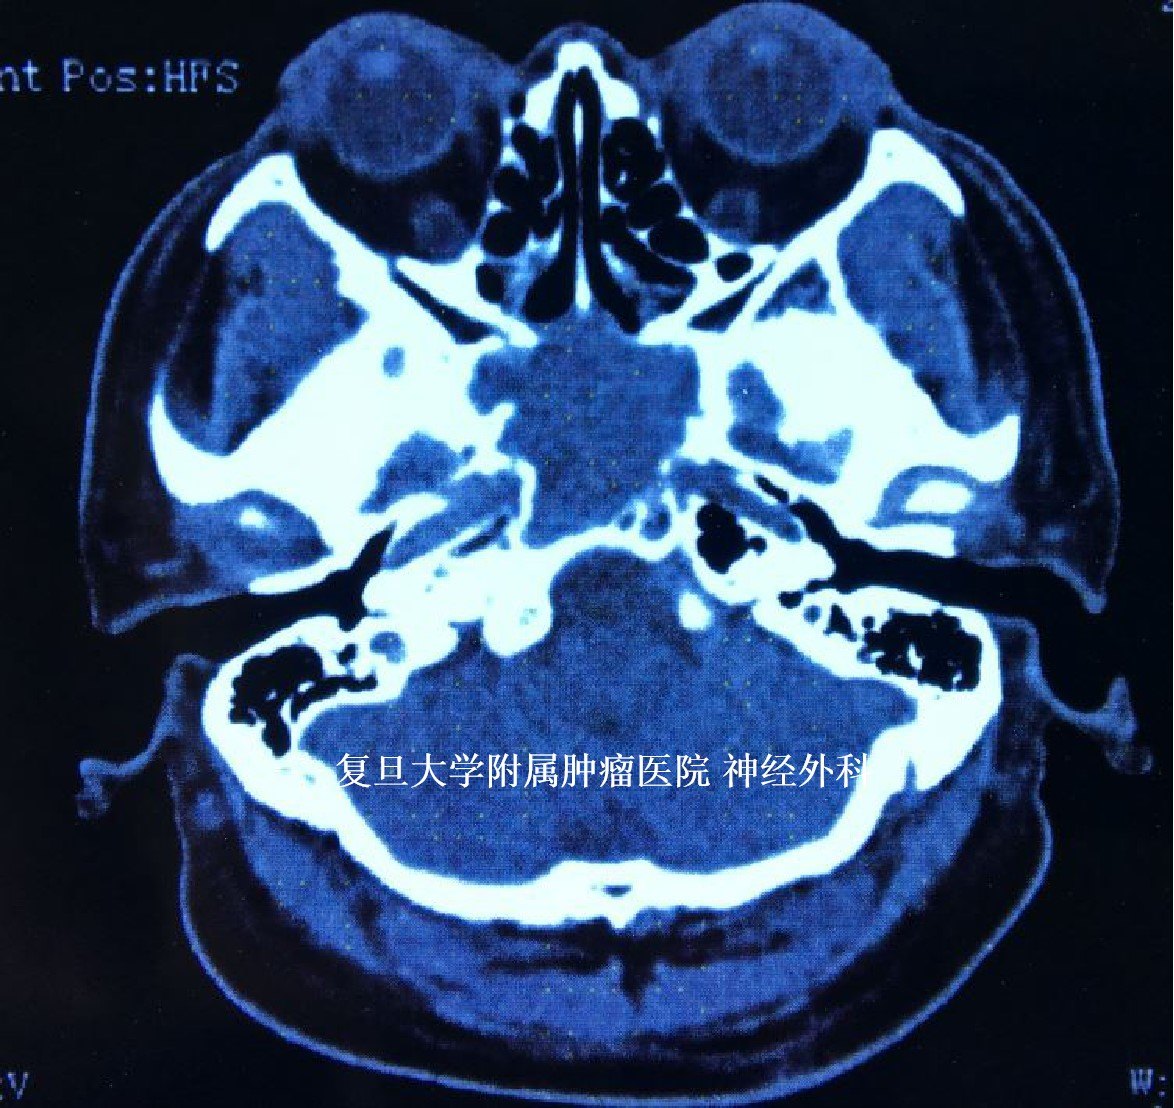

头颅CT显示:鞍区占位,颅底骨质破坏。